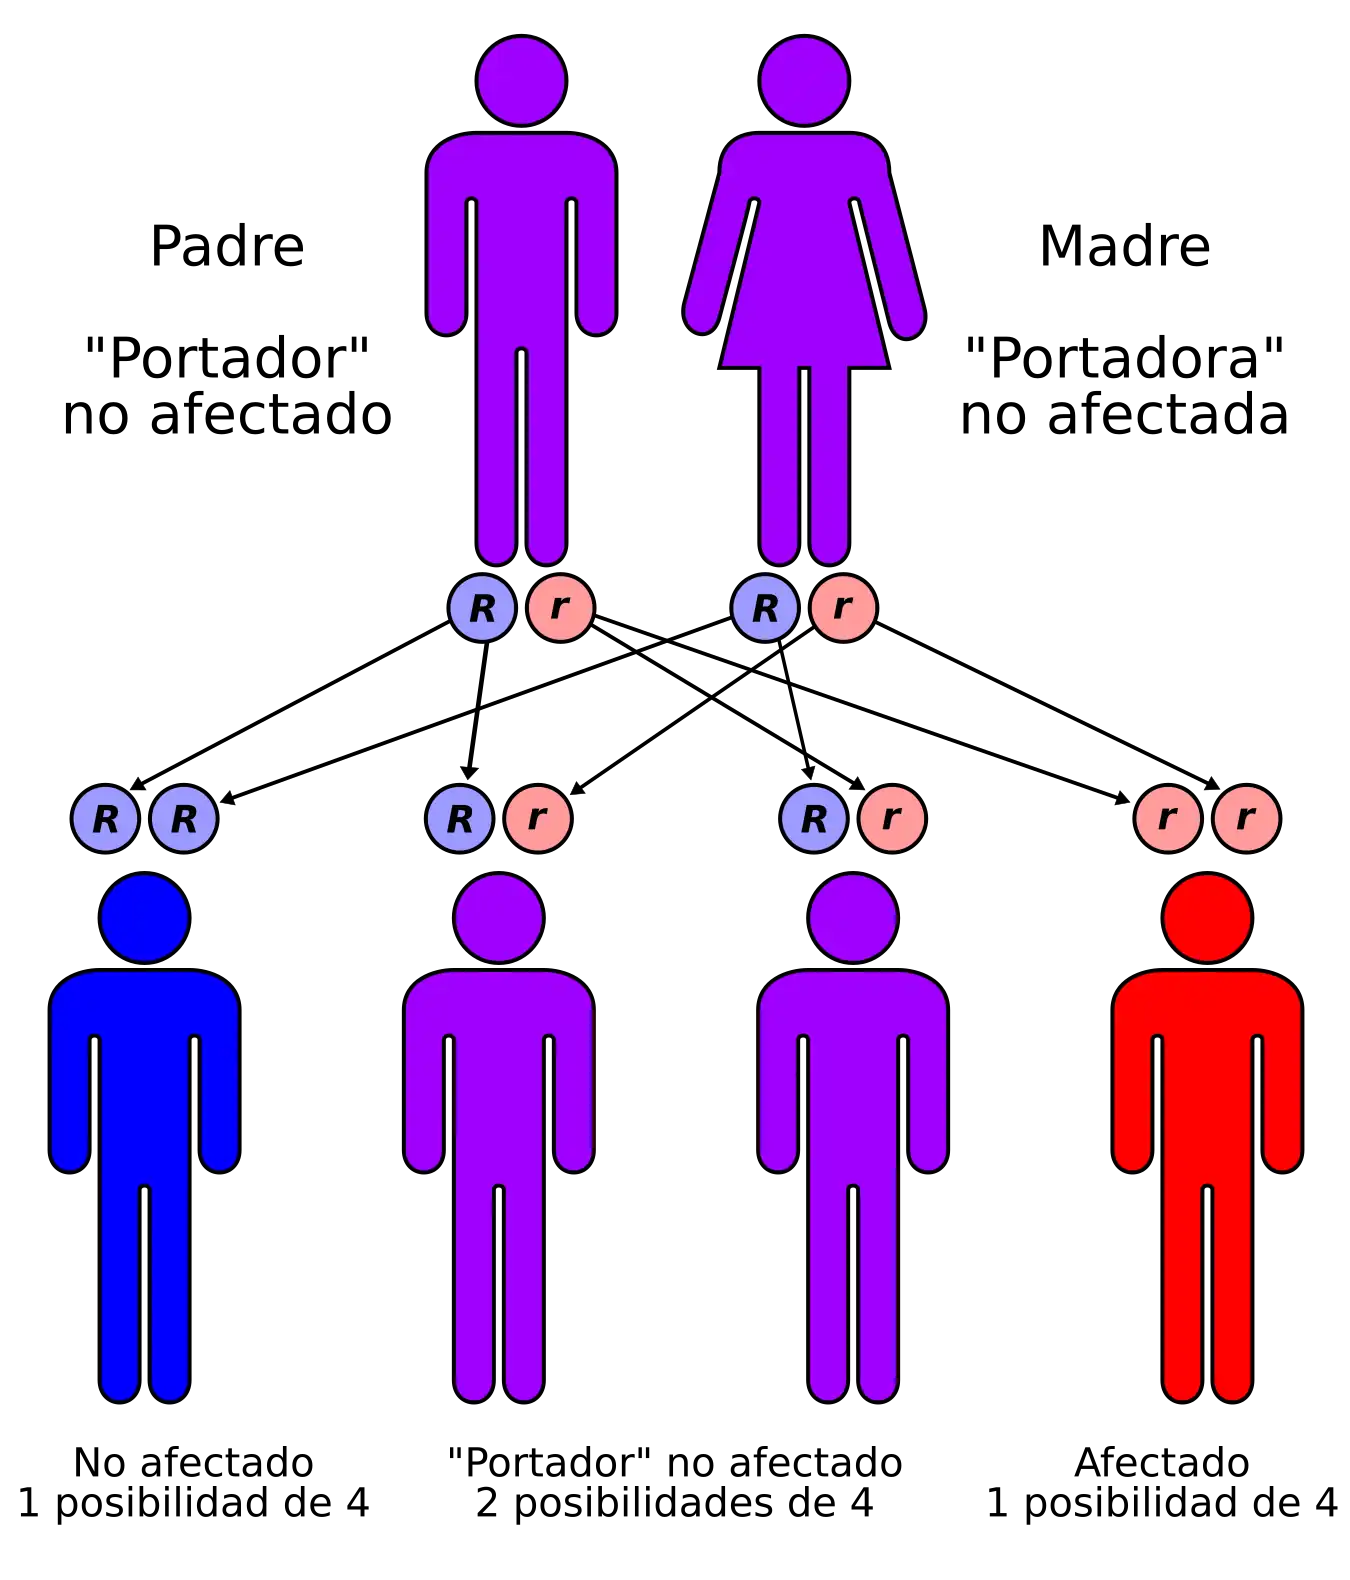

La fibrosis quística (abreviatura FQ) es una enfermedad genética de herencia autosómica recesiva que afecta principalmente a los pulmones, y en menor medida al páncreas, hígado e intestino, provocando la acumulación de moco espeso y pegajoso en estas zonas. Es uno de los tipos de enfermedad pulmonar crónica más común en niños y adultos jóvenes, y es un trastorno potencialmente mortal; los pacientes suelen fallecer por infecciones pulmonares debido a Pseudomonas o Staphylococcus.

Es producida por una mutación en el gen que codifica la proteína reguladora de la conductancia transmembrana de la fibrosis quística (CFTR). Esta proteína interviene en el paso del ion cloro a través de las membranas celulares y su deficiencia altera la producción de sudor, jugos gástricos y moco. La enfermedad se desarrolla cuando ninguno de los dos alelos es funcional.[1] Se han descrito más de mil quinientas mutaciones para esta enfermedad, la mayoría de ellas son pequeñas deleciones o mutaciones puntuales; menos de un 1 % se deben a mutaciones en el promotor o a reorganizaciones cromosómicas.

Es una de las enfermedades genéticas más frecuentes en la raza caucásica, con una incidencia en dicha población de aproximadamente uno de cada cinco mil nacidos vivos. Se calcula que una de cada veinticinco personas de ascendencia europea, es portadora de un alelo no funcional.

Se trata de una enfermedad autosómica recesiva. En su forma más común, una mutación de un aminoácido (falta una fenilalanina en la posición 508) conduce a un fallo del transporte celular y localización en la membrana celular de la proteína CFTR. Se han descrito más de mil ochocientas mutaciones,[31] siendo la mayoría de ellas pequeñas deleciones, aunque con diferentes efectos, como cambios en el marco de lectura, cambios de aminoácidos, terminación prematura de la proteína o alteraciones en el empalme (splicing) de ARNm.

La penetrancia de la enfermedad es variable según el alelo, y a su vez, la expresión del alelo depende del entorno y del genoma de la persona afectada.

Diagnóstico prenatal

Las parejas que están atravesando un embarazo o tienen planes respecto de la gestación, pueden ser evaluadas en busca de mutaciones del gen CFTR, con el objeto de determinar las probabilidades de que su hijo nazca con fibrosis quística. La prueba se suele realizar en uno de los padres o en ambos y, en caso de detectarse un riesgo elevado de FQ, se efectúa también en el feto. Debido a que el diagnóstico prenatal no habilita formas de tratamiento superiores o alternativas, la principal razón por la que se lleva a cabo es, en la práctica, proporcionar la posibilidad del aborto en caso de que el feto presente la enfermedad. La prueba para fibrosis quística en parejas se ofrece de manera generalizada en países como los Estados Unidos,[34] y el Colegio Americano de Obstetras y Ginecólogos (ACOG, por sus siglas en inglés) recomienda la prueba en parejas que poseen un historial de FQ entre sus familiares directos o parientes cercanos, así como también en aquellas con riesgo elevado debido a su filiación étnica.[35]

Debido a que el desarrollo de la FQ en el feto requiere que cada padre transmita una copia del gen CFTR mutante, y al alto costo del examen prenatal, la prueba suele realizarse, inicialmente, solo en uno de los progenitores. Si este resulta ser portador de una mutación del gen CFTR, entonces se examina al otro para determinar el riesgo de que su hijo tenga la enfermedad. La FQ puede resultar de más un millar de mutaciones diferentes y, al año 2006, no es posible efectuar estudios de laboratorio para cada una de ellas. La prueba se remite a analizar la sangre en busca de las más comunes, como ΔF508 —la mayoría de las modalidades disponibles comercialmente detectan no más de 32 variantes distintas—. Si se conoce el dato de que una familia tiene una mutación poco común, esta última puede buscarse específicamente. Como consecuencia de que no todas las mutaciones conocidas son detectadas por las pruebas corrientes, un resultado negativo no garantiza que el niño vaya a estar libre de la enfermedad.[36] Por otro lado, dado que las mutaciones sondeadas son necesariamente aquellas más comunes en los grupos de más alto riesgo, las pruebas en etnias de bajo riesgo son menos exitosas, ya que las mutaciones más extendidas en estos grupos son menos frecuentes en la población general.